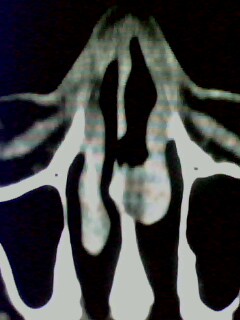

以下是引用随光逐影在2009-5-20 19:22:00的发言:[br]1)考虑左上颌骨近中线区含牙囊肿。2)鼻中隔右突偏曲。3)双侧下鼻甲肥大。